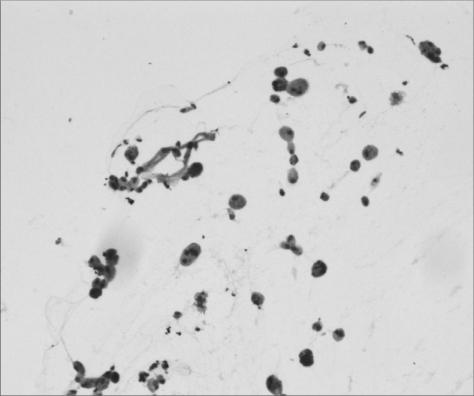

To report acute onset lens particle glaucoma associated with a spontaneous anterior capsular dehiscence. A 66-year-old man presented with spontaneous anterior lens capsule dehiscence with an acute onset of right eye pain that was associated with white particles in the anterior chamber angle and intraocular pressure (IOP) of 55 mmHg. No trauma or other inflammatory antecedents were reported. A hypermature cataract was observed at slit lamp exam. After medical treatment without IOP control, we performed extracapsular cataract extraction and anterior vitrectomy. Anterior chamber aspirate confirmed the presence of macrophages. The postoperative IOP at one month was 16 mmHg OD without medication. Spontaneous dehiscence of the anterior lens capsule in a patient with a hypermature cataract may release lens cortical material, resulting in lens particle glaucoma. Prompt surgical removal of the lens material usually controls the high IOP, and the need for additional glaucoma surgery is not common.